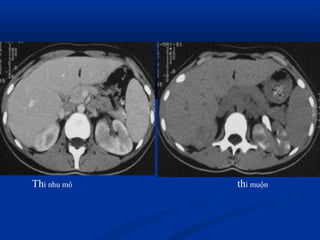

Vieâm thaän – beå thaänVieâm thaän – beå thaän

caápcaáp

 CT :CT :

 Khảo sát hình thái và chức năngKhảo sát hình thái và chức năng

 KT nhạy nhất để tìm ổ nhiễm trùng : dùngKT nhạy nhất để tìm ổ nhiễm trùng : dùng

dynamic CT, có hình ảnh giữ thuốc cản quang tạidynamic CT, có hình ảnh giữ thuốc cản quang tại

thì muộn.thì muộn.

 Dấu hiệu gián tiếp: đường bờ mờ, dày mạc thận,Dấu hiệu gián tiếp: đường bờ mờ, dày mạc thận,

thâm nhiễm mỡ quanh thận.thâm nhiễm mỡ quanh thận.

Thì nhu mô thì muộn

ThThì muộnì muộn